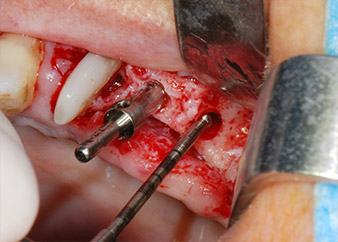

След един месец, в деня на операцията, болката и възпалението в зъб 24 е минимално, но подвижността в Miller class 2 е на лице. След отваряне на ламбата и почистването на периапикалната и перирадикуларната тъкани, обхватът на костния дефект стана очевиден (Фиг. 2 и 3).

В букалния корен, цялата вестибуларна и дистална кост липсва. Захващането е значително ограничено до палатиналния корен, подчертавайки предварително лошата прогноза. Зъб 27 също откри намалено хоризонтално захващане и минимално апикално разреждане (Фиг. 1) без клинични симптоми.

тотална загуба на кост и захват

Фиг. 2 и 3: След повдигане на ламбото, един месец след ендодонтския преглед и прилагане на цялостна периодонтална терапия в цялата уста, букалният корен на зъб 24 разкри тотална загуба на кост и захват.

Въпреки това, ние се придържахме към първоначалния си план да запазим и двата зъба като абатмънти за временен мост по време на 6-месечната остеоинтеграция на имплантите. При повторна интервенция, ситуацията трябва да се преразгледа. Първо, в опит да се овладее ендо-перио проблема, останалата повърхност на зъба е внимателно обработена с пиезохирургично оборудване (Piezomed, W&H, използван с накрайник S1 под формата на шпатула, първоначално проектиран за ерозия на латералната синусна стена) (Фиг. 4).